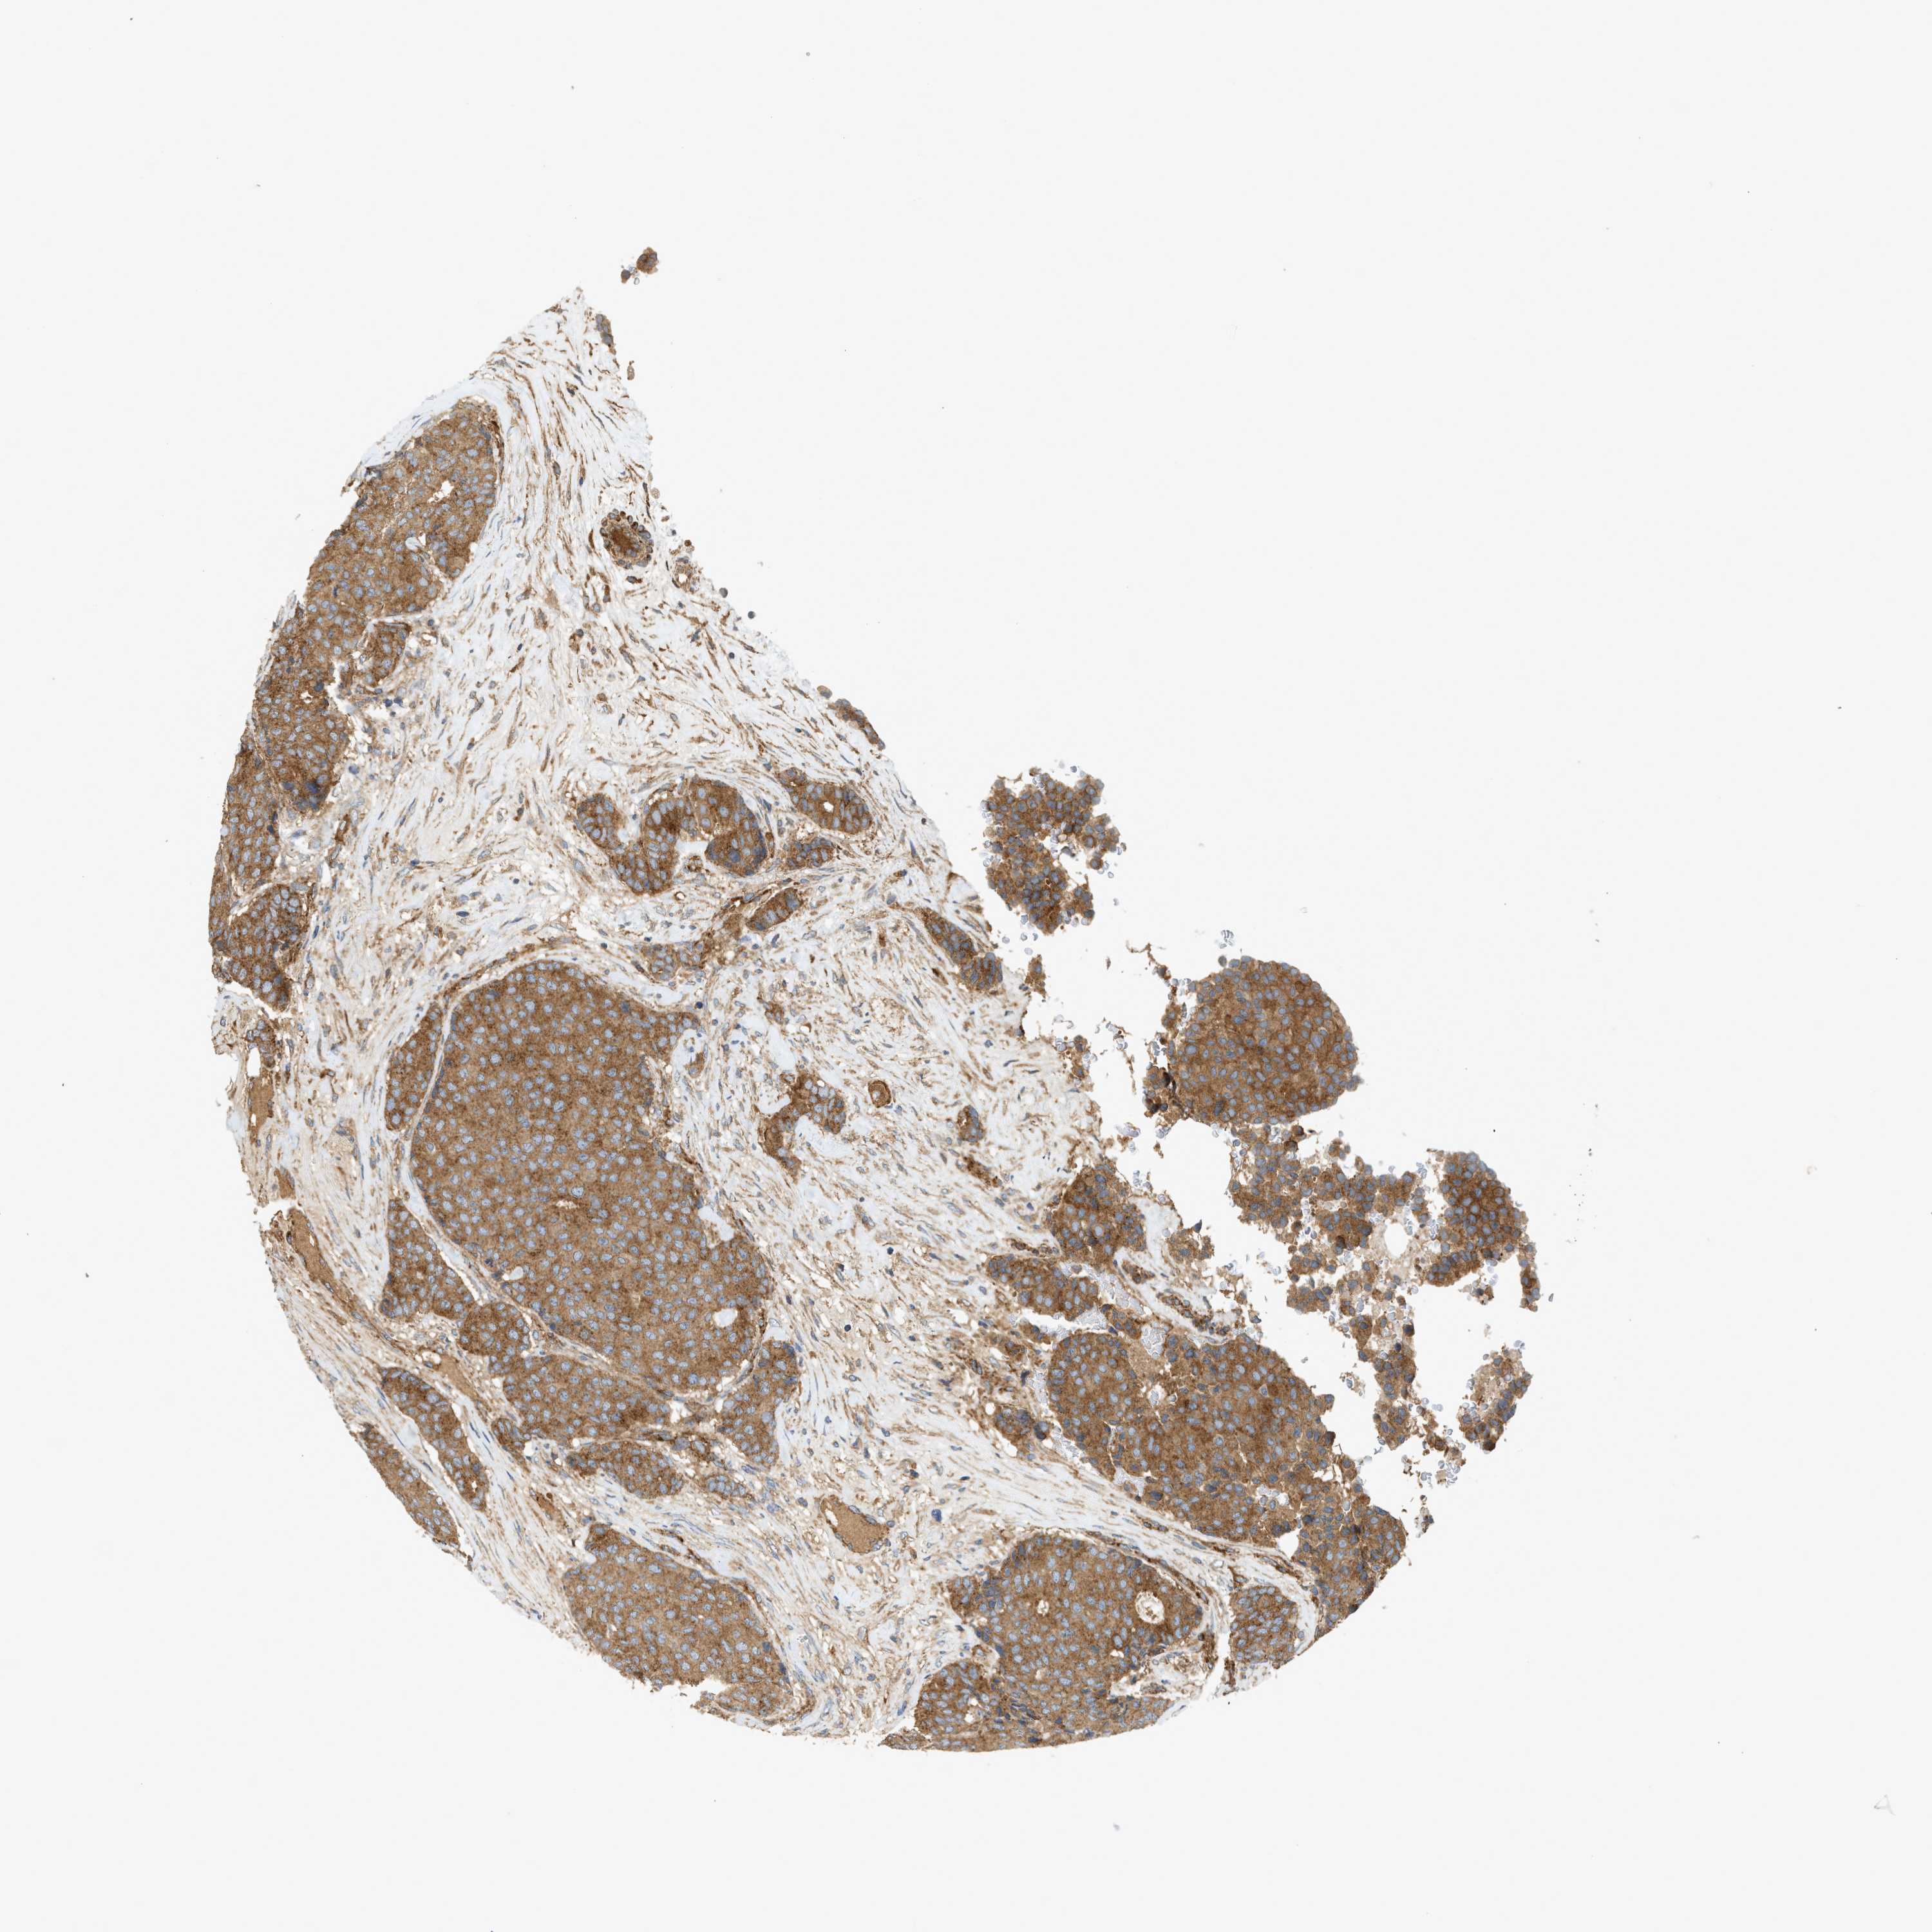

CANCER BREAST CANCER Show tissue menu

BRCA TCGA BRCA VALIDATION PROTEIN EXPRESSION